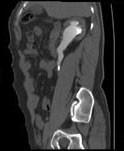

问题 男,36岁,反复发作的右侧腰背部疼痛伴血尿1年余,CT如图所示,下列说法正确的是 ( )

选项 A、右输尿管结石 B、右输尿管上段钙化 C、右输尿管上段扩张 D、右输尿管内可见沿输尿管走行的高密度影 E、右侧肾盂肾盏扩张

答案 ACDE